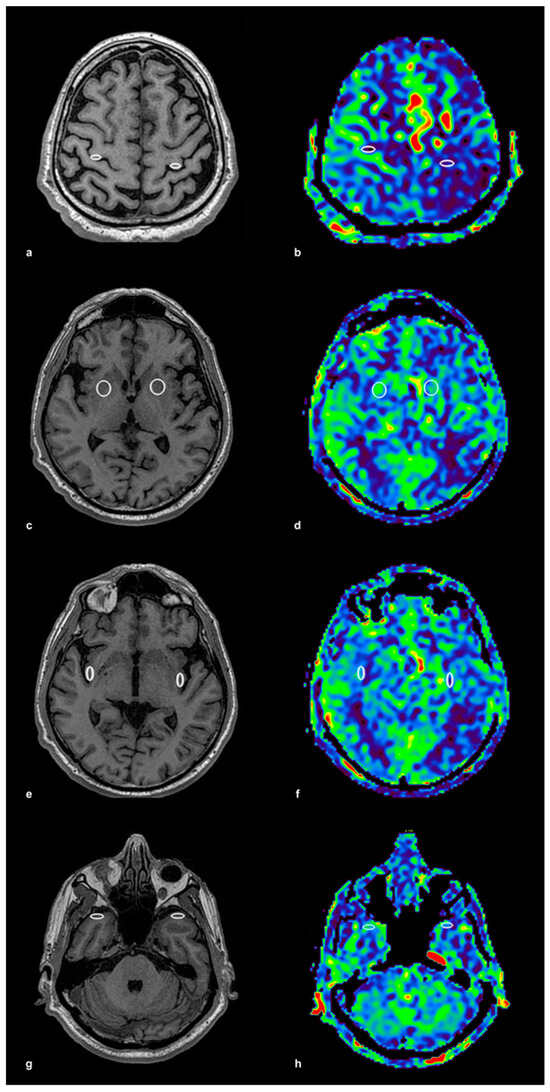

The ROIs were initially placed on high-resolution 3D T1-weighted anatomical images, ensuring precise localization within the gray matter, and then automatically transferred to the corresponding ASL perfusion maps acquired with identical geometric parameters. This method ensured accurate spatial alignment between anatomical and perfusion imaging. The ROI placement procedure is illustrated in Figure 1, using a control subject to demonstrate anatomical accuracy and spatial consistency. In panel (a), bilateral ROIs were positioned within the precentral gyrus on T1-weighted anatomical images, while panel (b) shows the corresponding ASL perfusion map with these ROIs overlaid for CBF quantification. Panels (c,d) depict the lentiform nucleus, again with paired anatomical and perfusion images. The same approach was applied to the insular cortex (e,f) and the temporal cortex (g,h), ensuring consistent methodology across all examined brain regions. To illustrate the same ROI protocol in a patient with significant unilateral carotid artery stenosis, Figure 2 presents corresponding anatomical and perfusion images. As in the control example, ROIs were bilaterally placed in the precentral gyrus, lentiform nucleus, insular cortex, and temporal cortex. Panel (a) shows ROI localization on T1-weighted images for the precentral gyrus, and panel (b) displays the matching ASL perfusion map. Panels (c,d) represent the lentiform nucleus, (e,f) the insular cortex, and (g) and (h) the temporal cortex, with anatomical and perfusion images paired in each case. This consistent ROI placement ensured reproducibility of the analysis and facilitated accurate intergroup comparisons of regional CBF values. ROI sizes ranged from 15 to 40 mm2, depending on the anatomical region, individual morphological variation, and the presence of age-related brain atrophy. Elliptical ROIs were applied to thinner cortical structures, such as the insular and precentral cortices, while circular ROIs were used in larger subcortical areas, including the lentiform nucleus and temporal cortex. This adjustment provided robust and anatomically valid perfusion estimates across the study population.

Figure 2. ROI Placement and ASL Perfusion Map in a Patient with Carotid Stenosis. This figure presents ROI placement and ASL perfusion maps in a patient with unilateral carotid stenosis, following the same methodology as in Figure 1. (a) T1-weighted image with ROI placement in the precentral gyrus (frontal cortex) bilaterally, and (b) the corresponding ASL perfusion map with the same ROIs transferred for CBF quantification. (c) T1-weighted image with ROI placement in the lentiform nucleus bilaterally, and (d) the corresponding ASL perfusion map. (e) T1-weighted image with ROI placement in the insular cortex bilaterally, and (f) the corresponding ASL perfusion map. (g) T1-weighted image with ROI placement in the temporal cortex bilaterally, and (h) the corresponding ASL perfusion map. ROI sizes (15–40 mm2) were adjusted according to the anatomical region, with elliptical ROIs applied in thinner cortical regions and circular ROIs in larger areas. The colored ASL perfusion maps (b,d,f,h) represent quantitatively measured cerebral blood flow (CBF), with warmer colors (red, yellow) corresponding to higher CBF values and cooler colors (green, blue) indicating lower values.